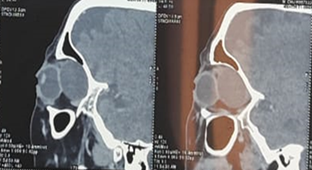

A 13-year-old

adolescent presented with progressive, chronic (4 years) and non-pulsatile

unilateral proptosis of the right eye. On clinical examination, a 20 mm

non-axial right exophthalmos was noted; palpation revealed a deep,

non-pulsatile, slightly tender, firm superior-internal orbital mass with

decreased visual acuity without chemosis or oculomotor disturbance.Computed

tomography revealed a 26 x 42 mm isodense retrobulbar cystic mass at the level

of the superior-internal angle of the right orbit, with a thick calcified wall

pushing the optic nerve backwards.